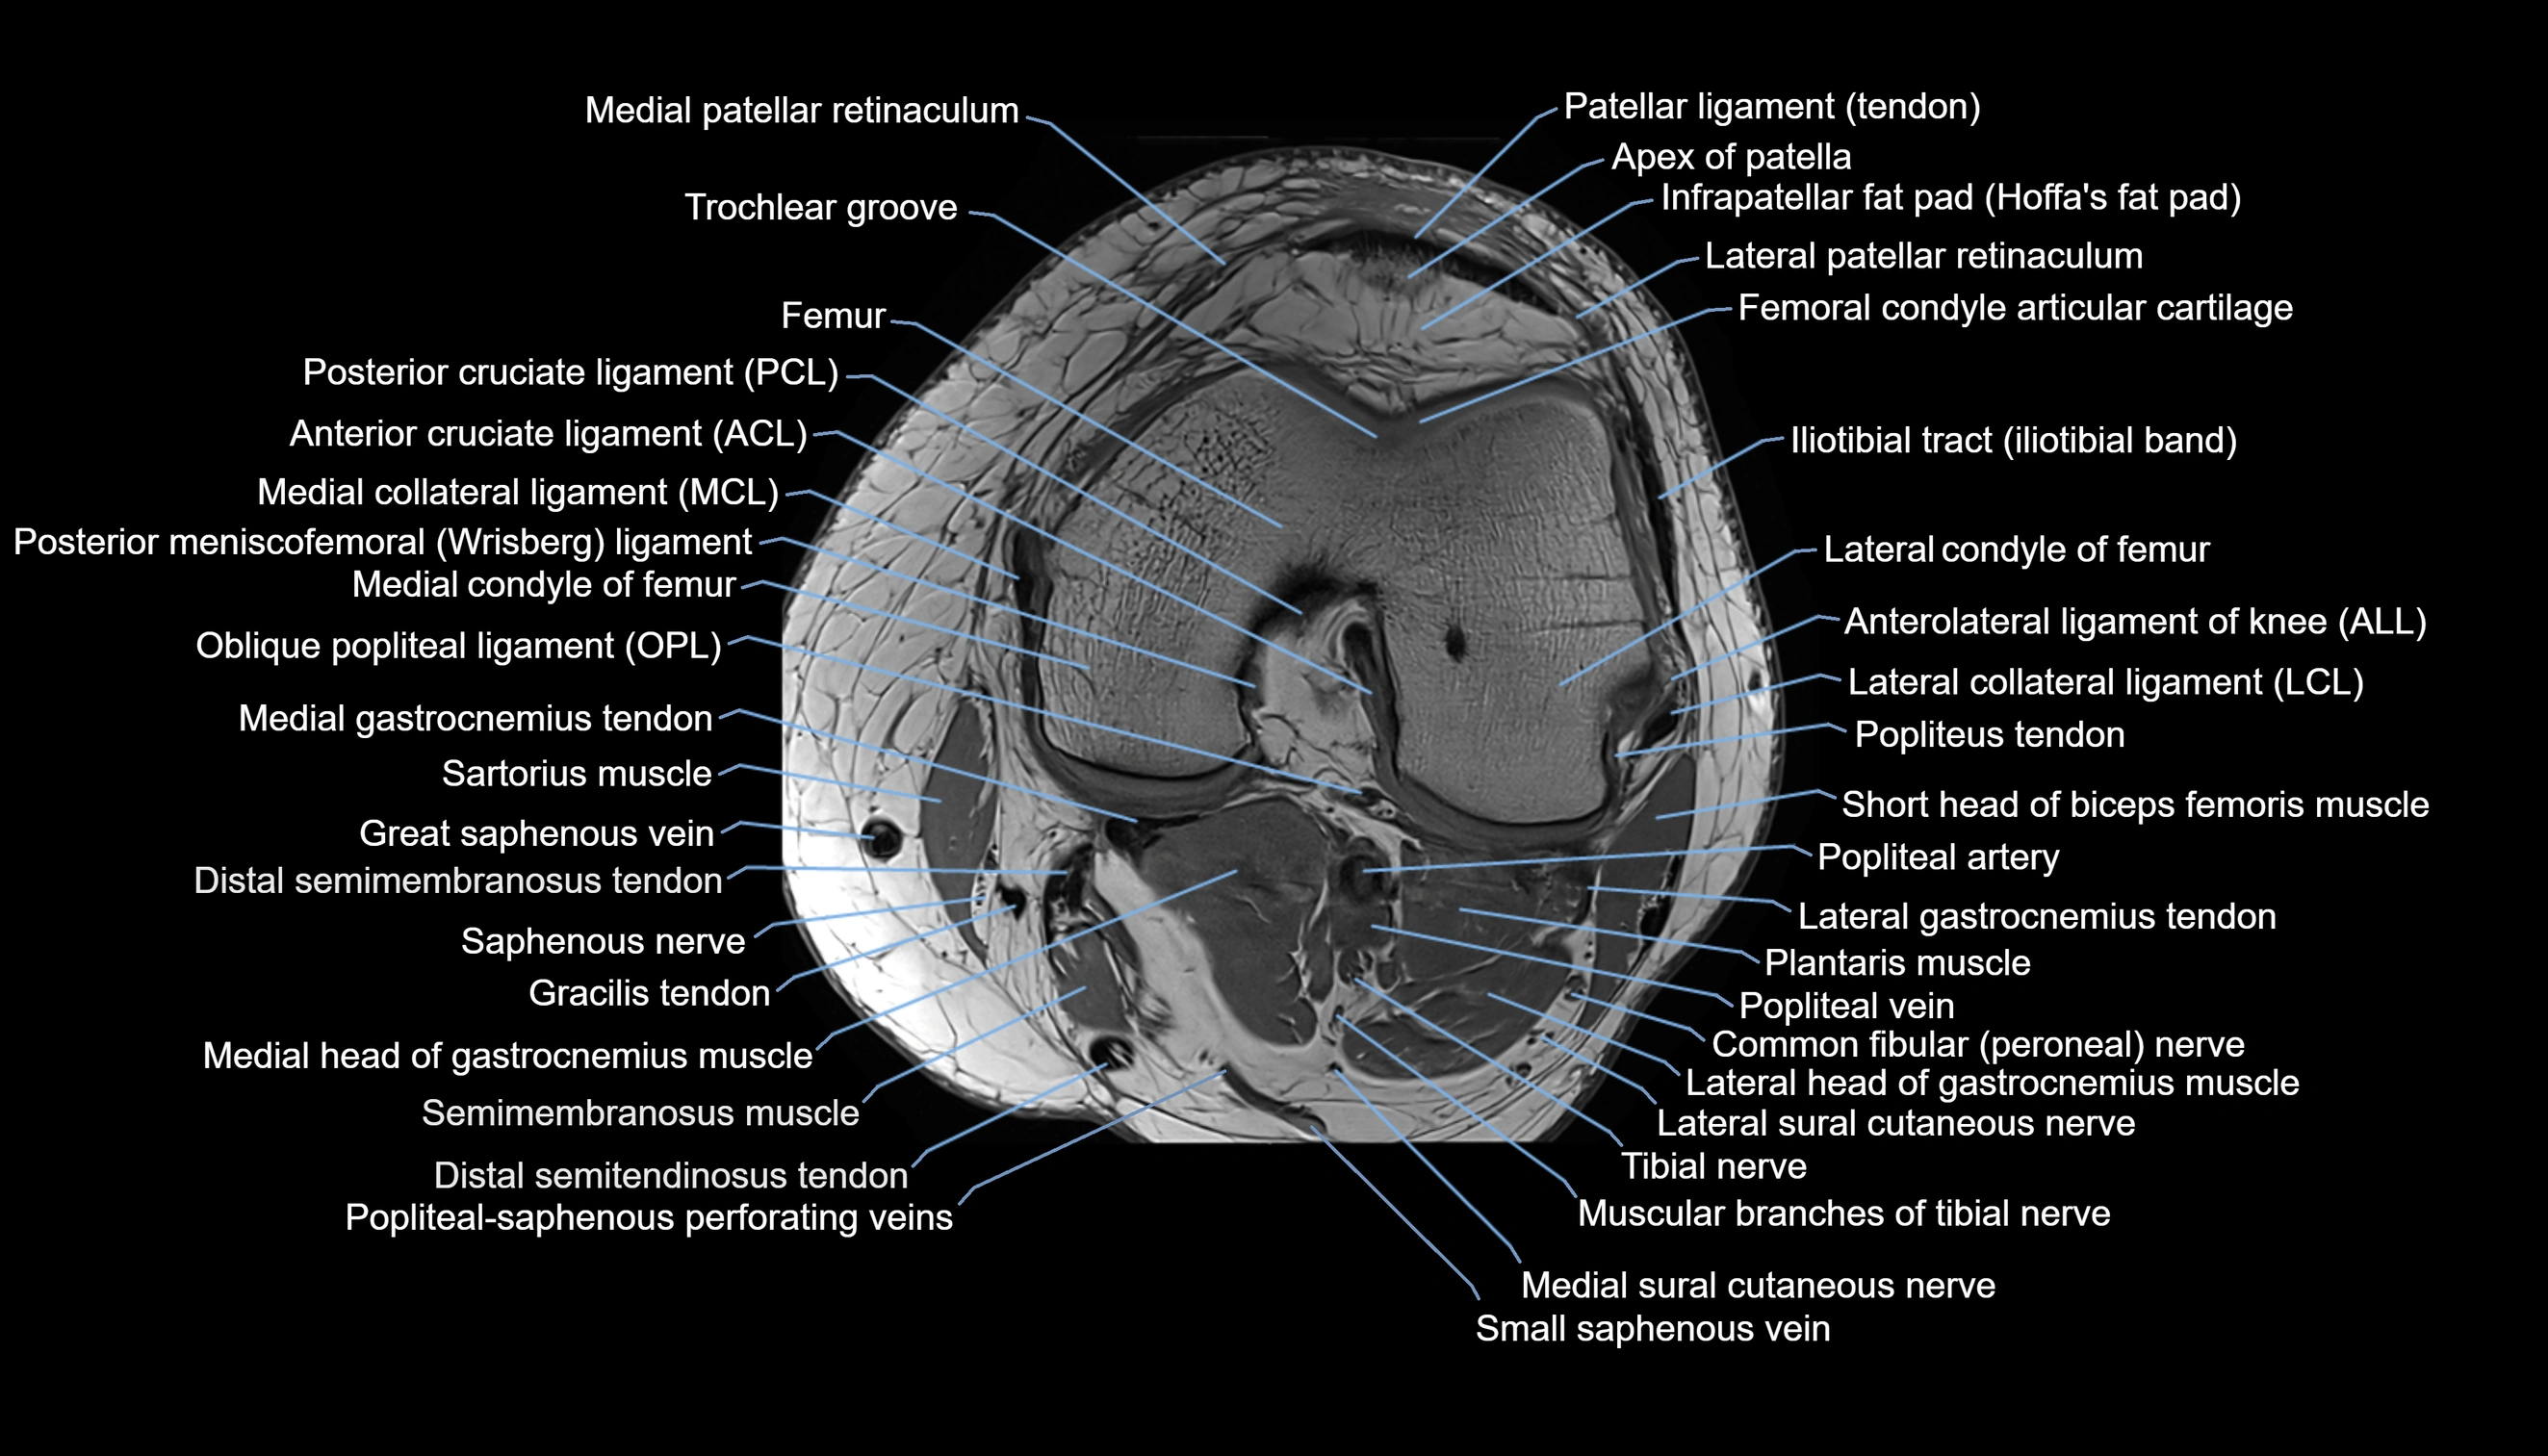

- Knee Joint

- Anterolateral ligament of knee

- Lateral collateral ligament

- Lateral condyle of femur

- Medial collateral ligament

- Medial condyle of femur

- Medial gastrocnemius tendon

- Medial head of gastrocnemius muscle

- Medial patellar retinaculum

- Medial sural cutaneous nerve

- Muscular branches of tibial nerve

- Oblique popliteal ligament

- Popliteal artery

- Popliteal vein

- Popliteus tendon

- Posterior cruciate ligament

- Posterior meniscofemoral ligament

- Saphenous nerve

- Sartorius muscle

- Semimembranosus muscle

- Small saphenous vein

- Tibial nerve